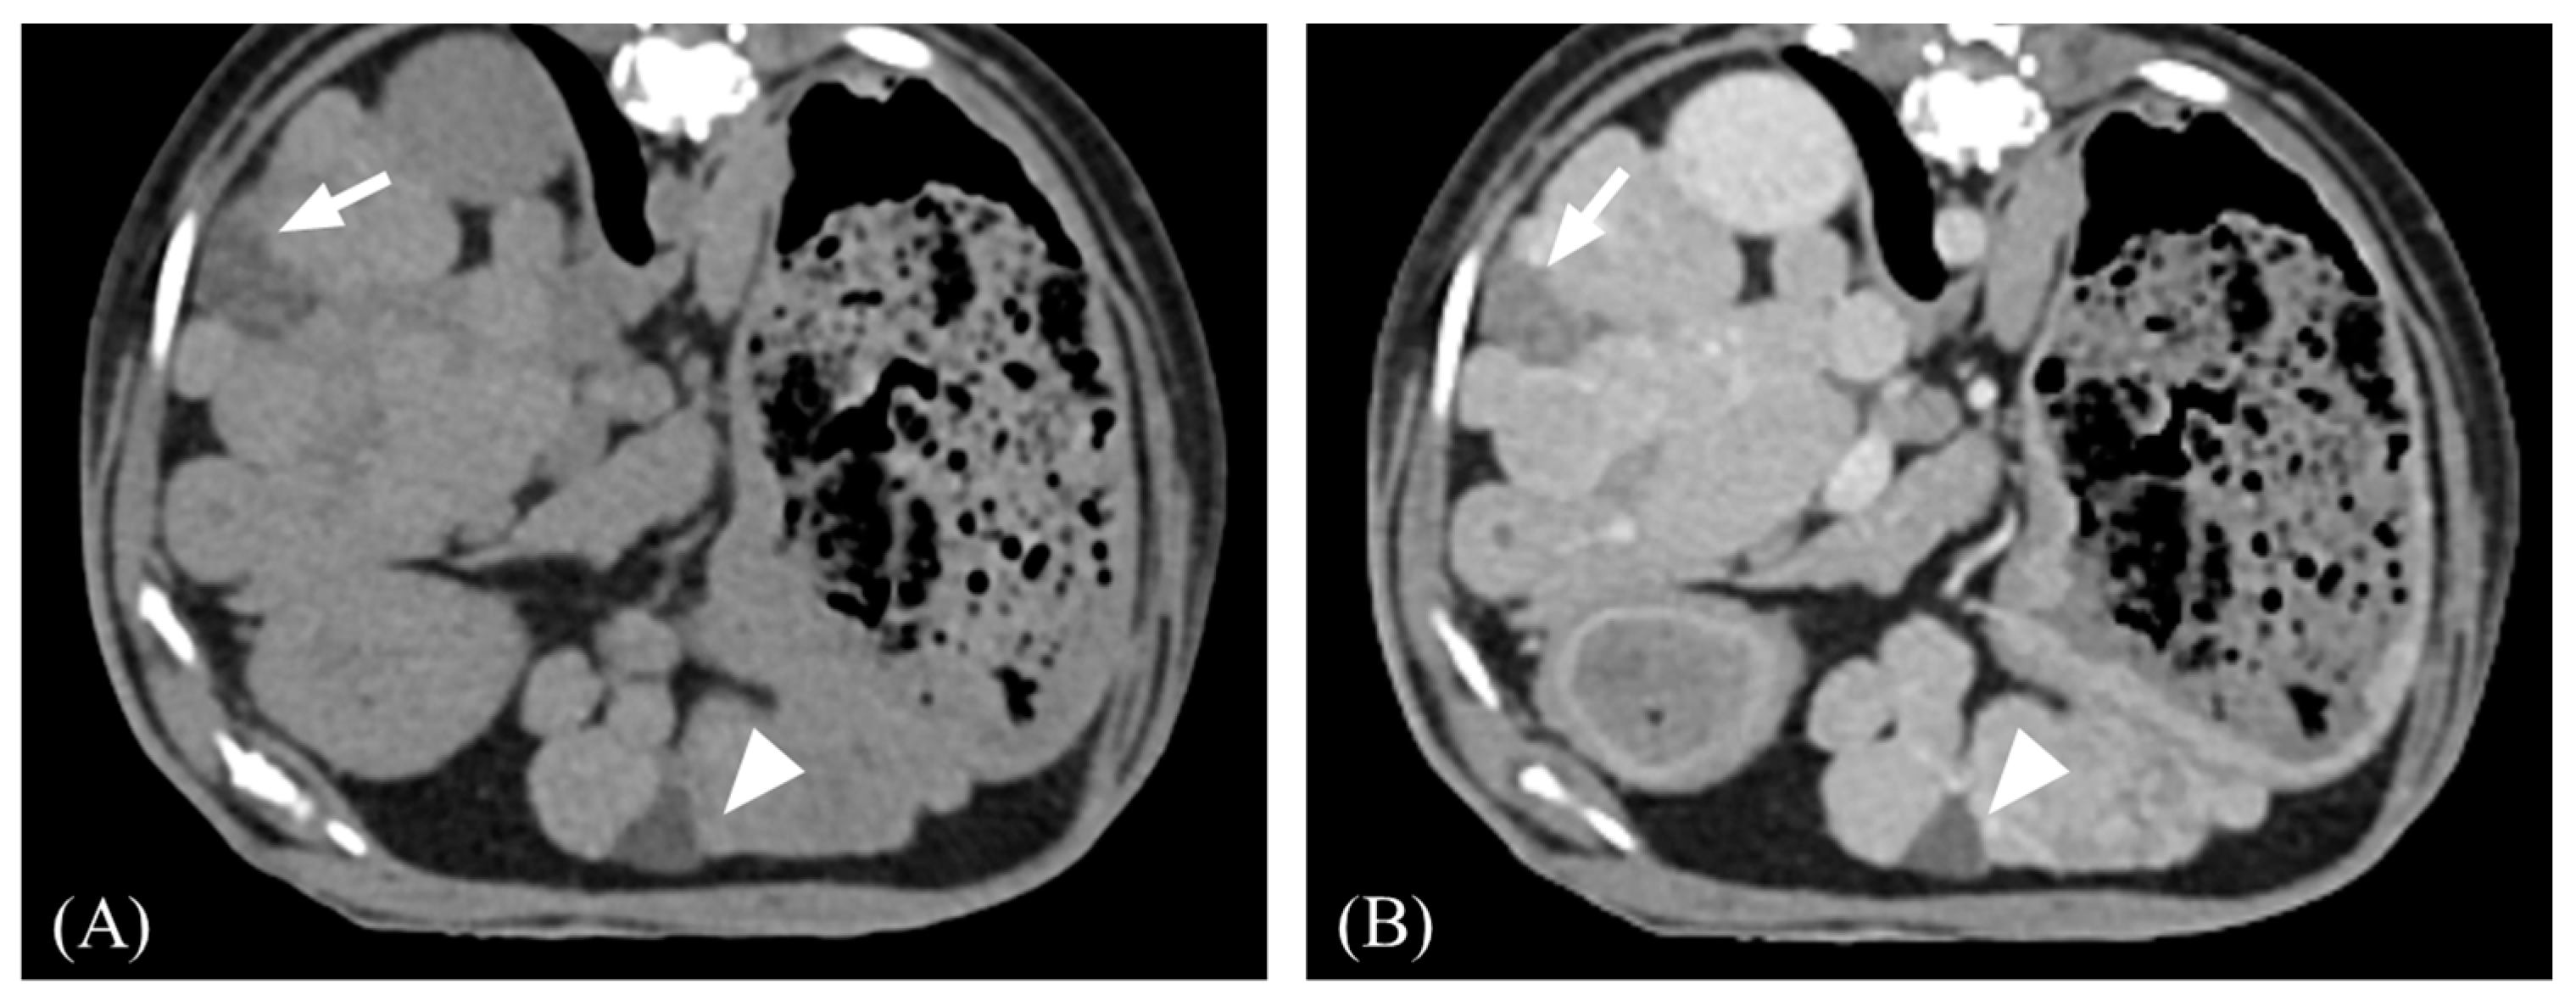

3.2. Qualitative Computed Tomographic Features

| Transient hepatic attenuation difference | Present | 7/13 (53.8%) | 4/8 (50%) | 3/5 (60%) | 1.000 |

| Absent | 6/13 (46.2%) | 4/8 (50%) | 2/5 (40%) |